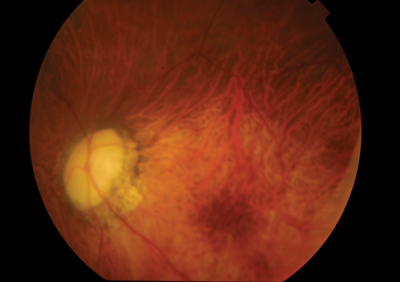

Figure 2: Fundus photograph of the left eye with no CMV retinitis; atrophic disc as a result of juvenile glaucoma.

A 29-year-old male patient with bilateral advanced juvenile glaucoma presented with a vitritis in the right eye four weeks after undergoing glaucoma surgery. The patient had an extensive ocular background of bilateral high myopia, poor left visual acuity (perception of light) from juvenile glaucoma, right failed trabeculectomy, right Baerveldt tube insertion and cataract surgery in March 2013 and a right macular haemorrhage in July 2013. He had a 2nd Baerveldt tube insertion in November 2013 with a 4mg dose of intravitreous triamcinolone acetonide (IVTA).